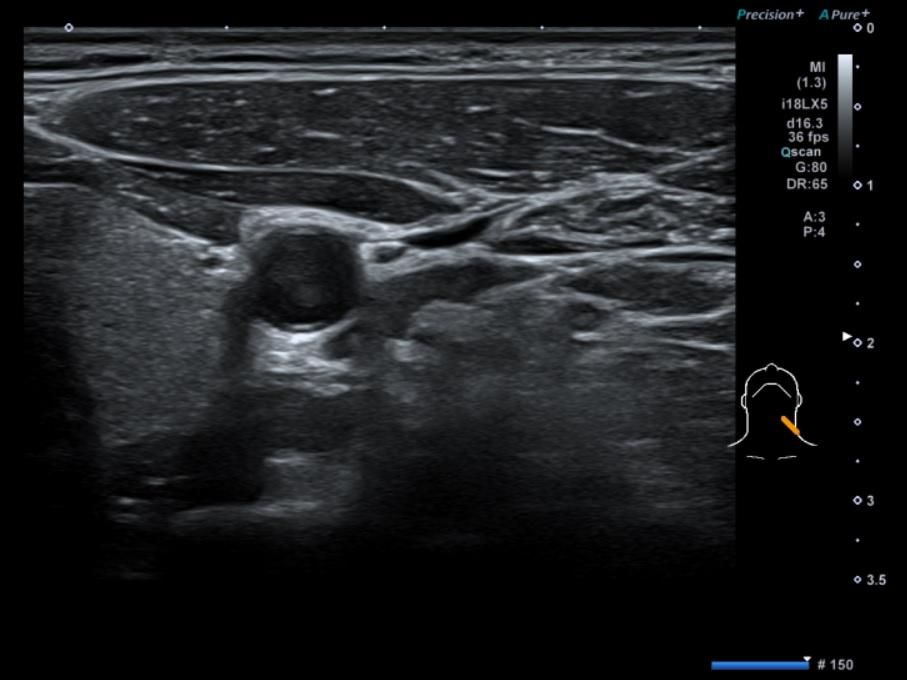

• 4번 째 사진